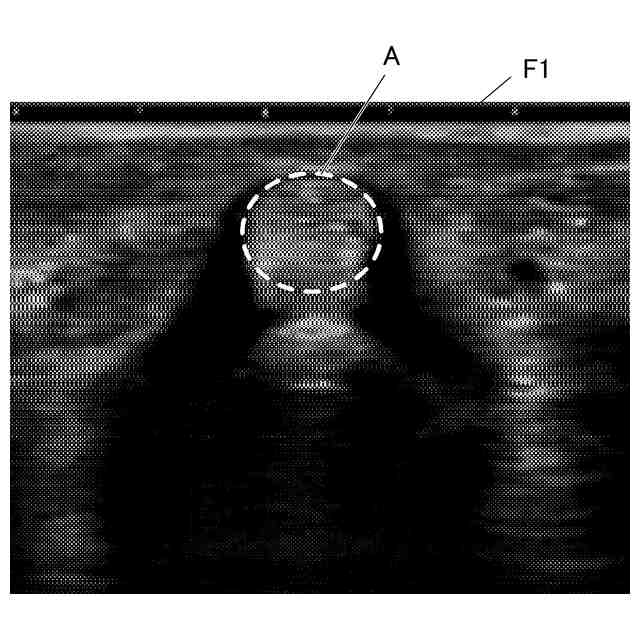

運動器及び麻酔領域の超音波検査では、筋、腱、神経束等の線維組織が撮像される。線維組織を撮像する場合には、超音波プローブを皮膚表面に押し当てた状態で超音波プローブの角度を変化させるあおり操作が行われる。あおり操作において、超音波プローブの線維組織に対する角度が適正でない場合、反射信号が得られない異方性反射組織となり、高輝度の超音波画像を得ることができない。

【解決手段】超音波診断装置は、被検体内に超音波を送信し、当該被検体内の対象組織で反射した超音波を受信して受信信号を得、当該受信信号に基づいて対象組織の超音波画像を出力する超音波診断装置であって、超音波プローブのあおり操作により当該超音波プローブの角度を変化させたときの複数のフレームの超音波画像を取得する取得部と、取得部により取得された複数のフレームから超音波プローブと対象組織とが直交する場合の超音波画像を含む基準フレームを抽出する抽出部と、抽出部により抽出された基準フレームを出力する出力部と、を備える。